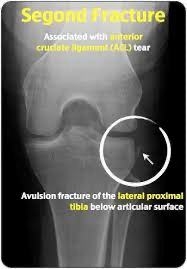

• ACL

• LACHMAN and ANTERIOR DRAWER TEST

• Lachman- hold femur and then take tibia and pull anteriorly.

• Anterior Drawer Test- Knee flexed and pull the tib fib forward after sitting on foot

• MRI IS GOLD STANDARD

• A diagram of a knee injuryDescription automatically generated

• X-ray of a knee jointDescription automatically generated